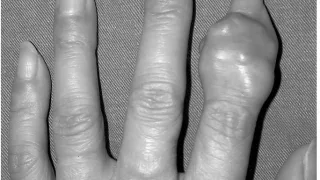

手術日+728日目 2026/2/25(水)(筋肉内神経鞘腫)